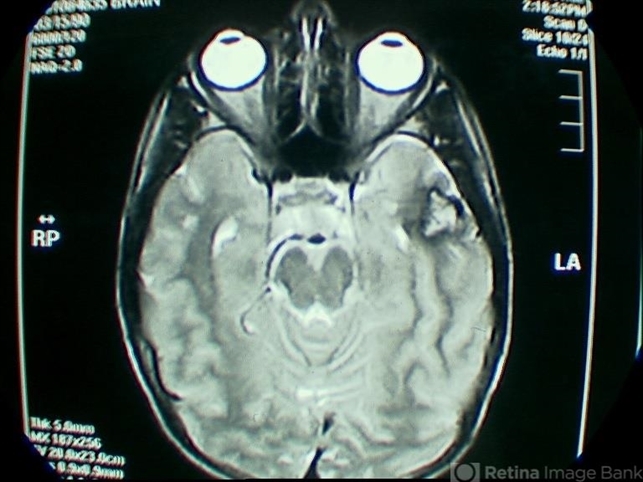

- Cavernous hemangioma of the retina and CNS

- cavernous hemangioma of the retina

- MRI of an 8-year-old boy with a cavernous hemangioma of the retina and a cavernous hemangioma of the temporal lobe.